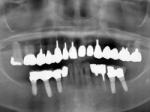

術前レントゲン

術前口腔内(正面観)